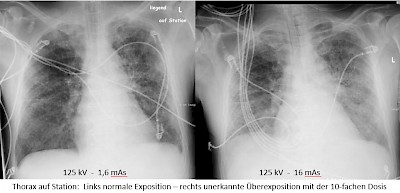

Digital ist das jetzt ganz anders. Selbst stark überbelichtete Aufnahmen, wie sie entstehen können, wenn zum Beispiel die Belichtungsautomatik versagt und die Strahlung erst durch die Grenzwertabschaltung (Abschaltautomatik) beendet wird, sind brauchbar und von bester Qualität. Lediglich bei stark unterbelichteten Aufnahmen kommt es zunehmend zu einer Bildverschlechterung durch ein Rauschen.

In der Digitaltechnik gibt es keine Über- oder Unterbelichtung mehr, sondern die Bilder werden mit einer immer gleichbleibenden Helligkeit im mittleren Grauwert geliefert. „Aufgrund der Signalnormierung ist nicht sofort feststellbar, ob die notwendige oder sogar eine überproportionierte Strahlendosis appliziert wurde.